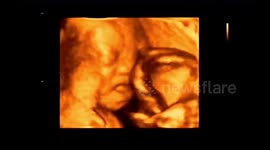

Baby Fighting!!!No 1

Baby Relax